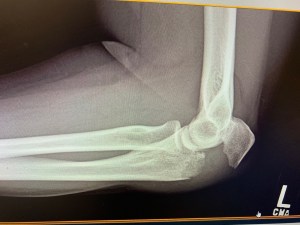

The doctor came in to take a look at it and just sort of give a surface inspection of it. He ordered X-Rays, but we needed to wait for the pain meds to kick in. So, we did that. And about 20 minutes later, they came and got her to take her back for the X-Rays. Chad and I chilled in the exam room until they brought her back. She made herself comfortable in the chair again and we awaited the doctor again. He came in shortly after and pulled up the images…starting with the back of her arm. It didn’t look bad at that angle. THEN…he flipped to the side view.

We all winced a little and went…”OOOOOH!” It was a VERY obvious break. Very obvious. But it was a clean break…not a shatter…so that was the good news. The doctor went to see if his surgeon had called back, because this would definitely entail surgery. When he did return with the news…surgery was necessary…but not that day. It could wait until after the weekend and they would split her up and give her a prescription to help with the pain…and she would have a surgical consult on Monday morning.

Heather was very worried about what this would mean for her and her job as far as being able to do it. Chad and I told her not to worry about that right now. He went to pull the car around and I went to help her get out to the car safely, in the process dropping my phone at least 3 times. It made her laugh…a little. We then made our way to Walgreens to pick up the prescription and a cast protector so that she could take a shower. And then…we went home.